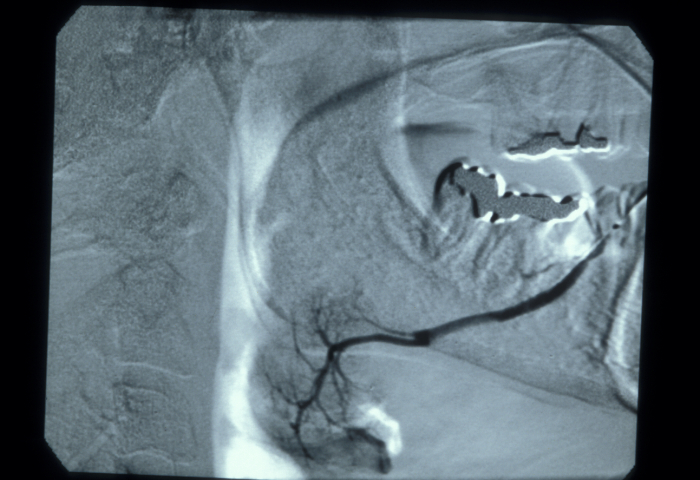

Iodine (in an aqueous solution) is used as an X-ray contrast agent for the examination of obstructions in the ducts of salivary glands, the recording of a sialogram. The iodine solution is injected into the salivary gland duct, followed by the recording of X-ray images to track the flow as well as structural local details. An aqueous, rather than an oily, iodine solution is used because it has low viscosity (hence will help to depict very fine detail) and does not cause any lasting problems if there is a leakage from the duct. Figure 3 shows an example of a sialogram. There may be some minor discomfort with the injection of the iodine contrast agent into the duct of a salivary gland. Iodine as a contrast agent has the advantage of being a bacteriocidal (killing bacteria) substance, although it is also quite allergenic.

Figure 3: A sialogram, investigating the duct of a salivary gland.